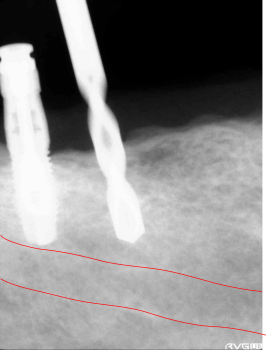

2015年09月18日手術 右下(46,47)インプラント植立 下歯槽管の近くまで、直径1.5mmのドリルで 穴を開けます。 安全性が確保出来る長さが決まったら 穴の直径を大きくします。 ![]() |

下歯槽管まで、近くなった所で安全性を確認するためレントゲン写真を撮影しまだ余裕があるのを確認します。 | ||